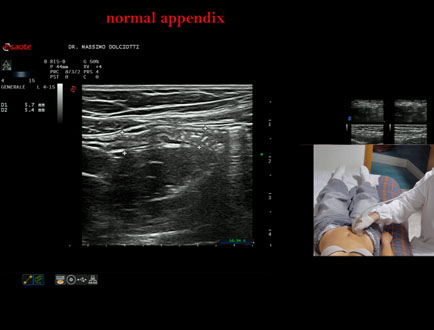

Data inserimento: 26/09/2025

Ecografia del: 12/09/2025

Strumento: Esaote MyLab Eight

Sonda: Lineare Multifrequenza 4-15 MHz

Età Paziente: F 24 anni

Motivazione dell'esame: da 3 mesi dolore al fianco destro.

Commento all'esame: le immagini ed il video documentano l'appendice di spessore normale (5,1-5,7 mm - v.n. < 6 mm).

Conclusioni: appendice normale (normal appendix).

Presentazione: Dr. Massimo Dolciotti - Ancona